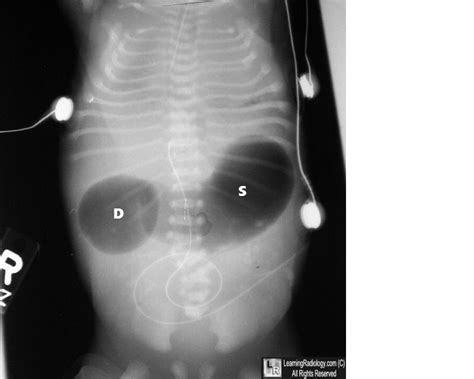

Double Bubble Sign

Double Bubble Sign. Most obstructions involve the second and third parts of the duodenum and are located close to the orifice of the bile duct (9), and may be This is when doctors can see 2 bubbles in your baby’s abdomen (belly area).

It is seen in both radiographs and ultrasound, and can be identified antenatally 2. For duodenal stenosis, partial duodenal obstruction or duodenal atresia with a rare bile duct malformation, air may still be seen in the intestines beyond the duodenum. These occur when there is fluid in the stomach and part of the duodenum, but there is no fluid further down the intestinal tract. Web the clearest sign of duodenal atresia during prenatal ultrasound is the double bubble sign. Web in radiology, the double bubble sign is a feature of pediatric imaging seen on radiographs or prenatal ultrasound in which two air filled bubbles are seen in the abdomen, representing two discontiguous loops of bowel in a proximal, or 'high,' small bowel obstruction. Web the double bubble sign is seen in infants and represents dilatation of the proximal duodenum and stomach. This is a classic sign of duodenal atresia seen on ultrasound. Web “double bubble:” a classic sign of a proximal small bowel atresia (duodenal atresia) is the “double bubble,” when there is dilated bowel and fluid in the baby’s stomach and part of duodenum (first portion of intestine after contents leave. Web classically, for duodenal atresia, one will see an enlarged (dilated) stomach and duodenum without air further along in the intestines. This is when doctors can see 2 bubbles in your baby’s abdomen (belly area).

Most obstructions involve the second and third parts of the duodenum and are located close to the orifice of the bile duct (9), and may be Web in radiology, the double bubble sign is a feature of pediatric imaging seen on radiographs or prenatal ultrasound in which two air filled bubbles are seen in the abdomen, representing two discontiguous loops of bowel in a proximal, or 'high,' small bowel obstruction. Web classically, for duodenal atresia, one will see an enlarged (dilated) stomach and duodenum without air further along in the intestines. This is a classic sign of duodenal atresia seen on ultrasound. These occur when there is fluid in the stomach and part of the duodenum, but there is no fluid further down the intestinal tract. Web duodenal obstruction, including both stenosis and atresia, is the most common intestinal obstruction in newborns and has an approximate incidence of 1 in 10 000 live births (8). Web “double bubble:” a classic sign of a proximal small bowel atresia (duodenal atresia) is the “double bubble,” when there is dilated bowel and fluid in the baby’s stomach and part of duodenum (first portion of intestine after contents leave. Web the double bubble sign is seen in infants and represents dilatation of the proximal duodenum and stomach. Most obstructions involve the second and third parts of the duodenum and are located close to the orifice of the bile duct (9), and may be It is seen in both radiographs and ultrasound, and can be identified antenatally 2. This can result when, in the presence of obstruction within the proximal small bowel (most often duodenal atresia), there is dilatation of both the.